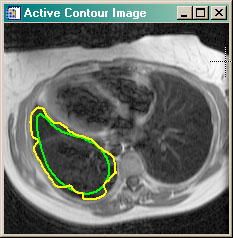

- cgSNAKE Applies active contouring Gradient Vector Flow "snake" contour algorithm to 2D dataset.

cgSNAKE | |

This program is similar to the

ActiveContour program in that it implements the Gradient Vector Flow

active contouring method of Xu and Prince. It differs in that it does so without

requiring an interactive GUI. In other words, the GVF algorithm can be applied to

a 2D dataset as a function, in the manner of other image processing functions.

The program requires that the GVF_Snake program be purchased from the Coyote Store. You can read more about active contouring in the article Active Contouring (Snakes) in IDL. |